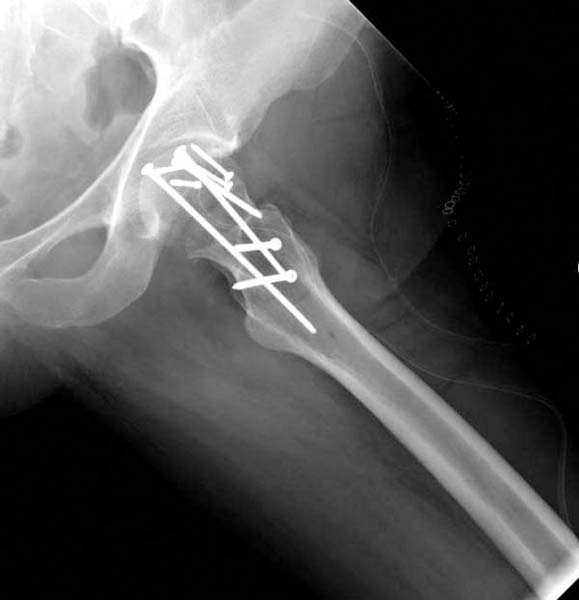

Больная стабильная после хирургических мероприятии и получив добро, приступили к закрытому вправлению таранной кости с укладкой наружного фиксатора. Затем укладка больную на бок и открытый остеосинтез перелома-вывиха головки бедра.

По характеру повреждения головка находится сзади и напрашивается задний Кохер-Лангенбек доступ, но в заднем доступе имеется риск повреждения магистрального кровоснабжения головки a. circumflexa. Более щадящая trochanteric flip (digastric osteotomy) сохранит кровоснабжение и дасть возможность работу при вывихнутом суставе.

Остеосинтез бедра не стали делать из-за множественных переломов ребер с ушибом грудной клетки и поэтом у закончили фиксацию бедра наружным фиксатором.

Около 11.00 вечера больная переведена в реанимацию, без сознания, но стабильная.. На третьий день провели стабилизацию перелома бедра антеградным остеосинтезом.